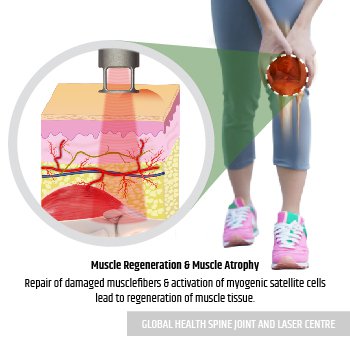

Laser Beam is applied to the knee for treating all damage.

Laser Beam increased oxygenated blood to the injured tissue accelerates tissue healing.

Repair of damaged muscle fibers & activation of myogenic satellite cells leads to regeneration of muscle tissue.